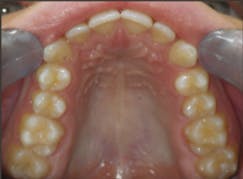

Case 1: 27-year-old male: 2-year clear aligner treatment. There was an estimated 8 mm to 10 mm increase in the transverse measurement. Case and photos courtesy of Dr. Daniel Noor.

Before: V-shaped arch. After: U-shaped arch.